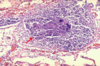

chronic bronchitis: submucosal gland hypertrophy